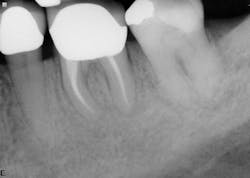

The second case involves a patient with tooth no. 19 having substantial furcation damage and moderate-sized apical periodontitis (figure 3).

Treatment included a two-visit approach, with two weeks in interim calcium hydroxide therapy.